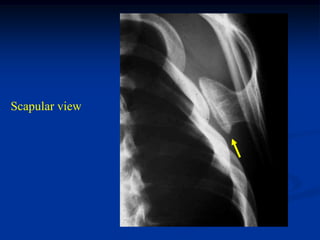

Case #612

25 year male

osteochondoma

scapula

Scapular view

cartilage cap

Resected specimen